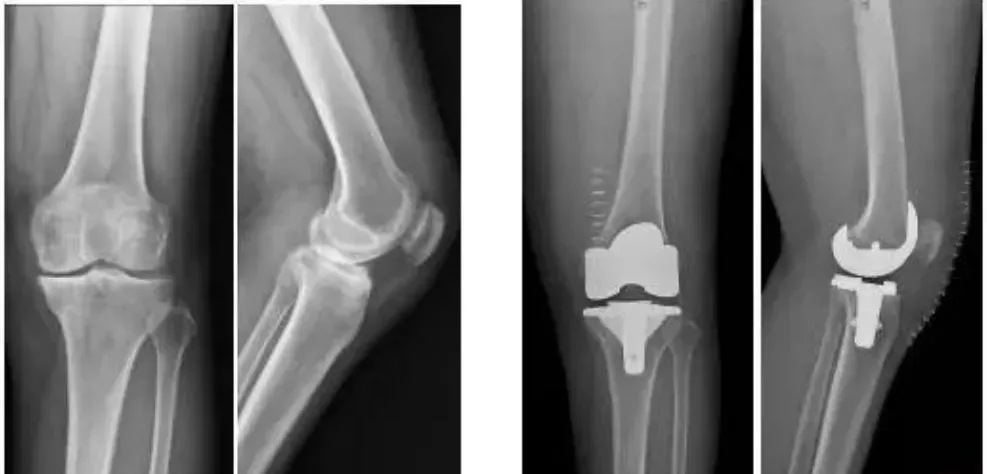

全球首款3D打印分區骨小梁生物型膝關節假體

這種新型假體與傳統骨水泥假體相比,其通過假體—骨界面緊密接觸,促使骨組織長入假體,提高假體與髓腔的結合強度,從而達到假體的長期穩定。使用生物型人工膝關節,可保存患者骨量,同時避免或降低了骨水泥所導致的毒副作用。

目前臨床上使用的膝關節假體多為骨水泥固定型假體,骨水泥即骨粘固劑,它可以將膝關節假體固定在骨界面上。骨水泥固定存在一定局限,如骨水泥單體具有一定的毒性;與骨接觸面的骨溶解問題;隨著時間推移,會發生變形和退變等。

本次植入的生物型膝關節假體在術中無需使用骨水泥,通過機械方式進行固定,即假體與骨組織的緊密結合,獲得假體的初始穩定性,遠期骨組織長入假體表面的微孔內部,實現由機械固定向生物內鎖固定的轉化,終經過骨整合作用獲得良好固定,預期能夠獲得更長的假體壽命。

此外,生物型膝關節假體避免了骨水泥相關并發癥的發生,縮短了手術時間,大程度保留了骨組織。因而減輕了患者術后疼痛,降低了圍術期并發癥發生率,有利于患者術后快速康復。

周宗科教授介紹說,該款3D打印分區骨小梁生物型膝關節假體有三個亮點,一是脛骨平臺假體采用了3D打印骨小梁分區技術,三分區設計使宿主骨均勻骨長入,避免因應力分布不均而造成平臺假體松動等問題;二是所用股骨髁假體表面為真空等離子噴涂純鈦涂層,其粗糙的接觸面增加了骨誘導的能力,具有優異的即刻穩定和長期穩定性;三是所用平臺墊為添加維生素E的高交聯超高分子量聚乙烯材質,具有優異的耐磨性能。